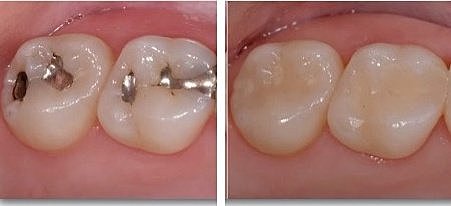

• Cambio de restauración filtrada

Cambio de restauración filtrada

Se cambiarán las restauración filtrada de las piezas dentarias 2.1, 2.2, 2.4. Se utilizará aislado absoluto, con una fresa de carburo número 4 se retirará la restauración previa y finalmente se obturará con resina del tono del órgano dentario.